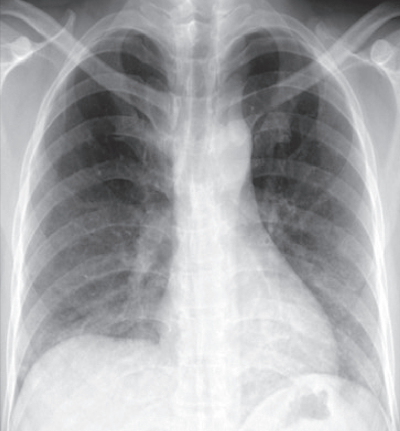

血液所見:赤血球414万、Hb 12.7 g/dL、Ht 25%、白血球 13,700(好中球 92%、単球 3%、リンパ球 5%)、血小板 37万。免疫血清学所見:CRP 0.4 mg/dL、β-D-グルカン 185 pg/mL(基準 10以下)。胸部エックス線写真、肺野条件の胸部CTおよび気管支肺胞洗浄液Grocott染色を別に示す。